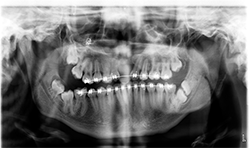

Panoramic and cephalometric radiographs are of limited use due to superimposition of anatomical structures (Figs. 5A, 5B, 5C).

CBCT characterizes the cleft defect more superiorly than 2D imaging (Fig. 6).

The Planmeca Viso G7 CBCT unit and Planmeca Romexis software can stitch two volume scans automatically with one click. The top portion of the skull (Fig. 7A) and the remaining maxillofacial portion (Fig. 6) were stitched to make a single skull volume (Fig. 7B). Multidisciplinary team has been working on this patient. Prosthodontics and oral surgery will plan to manage maxillary alveolar cleft and associated malocclusion following the CBCT images.